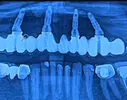

Implant tedavisi